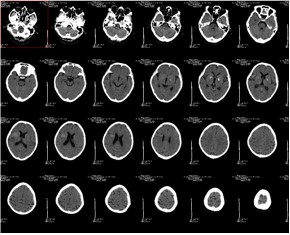

病例图片

![]() |